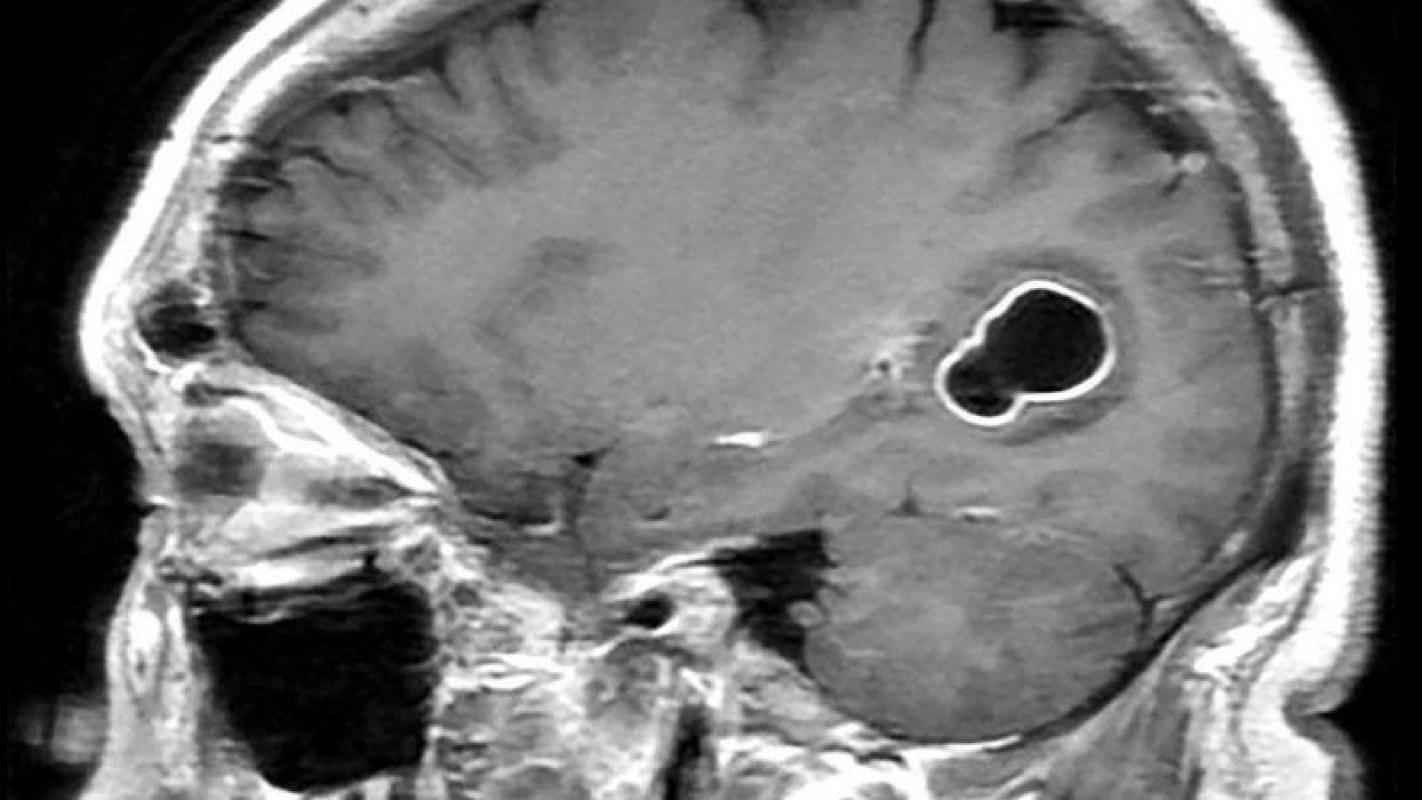

Bajo ese contexto, y al no entender por qué le dolía tanto la cabeza, los médicos decidieron realizarle varias tomografías, en las que se veían varios quistes en el cerebro. Sin embargo, con estudios posteriores, comprobaron que en verdad tenía larvas, las cuales causan una infección llamada neurocisticercosis.

Paciente tenía larvas en su cerebro